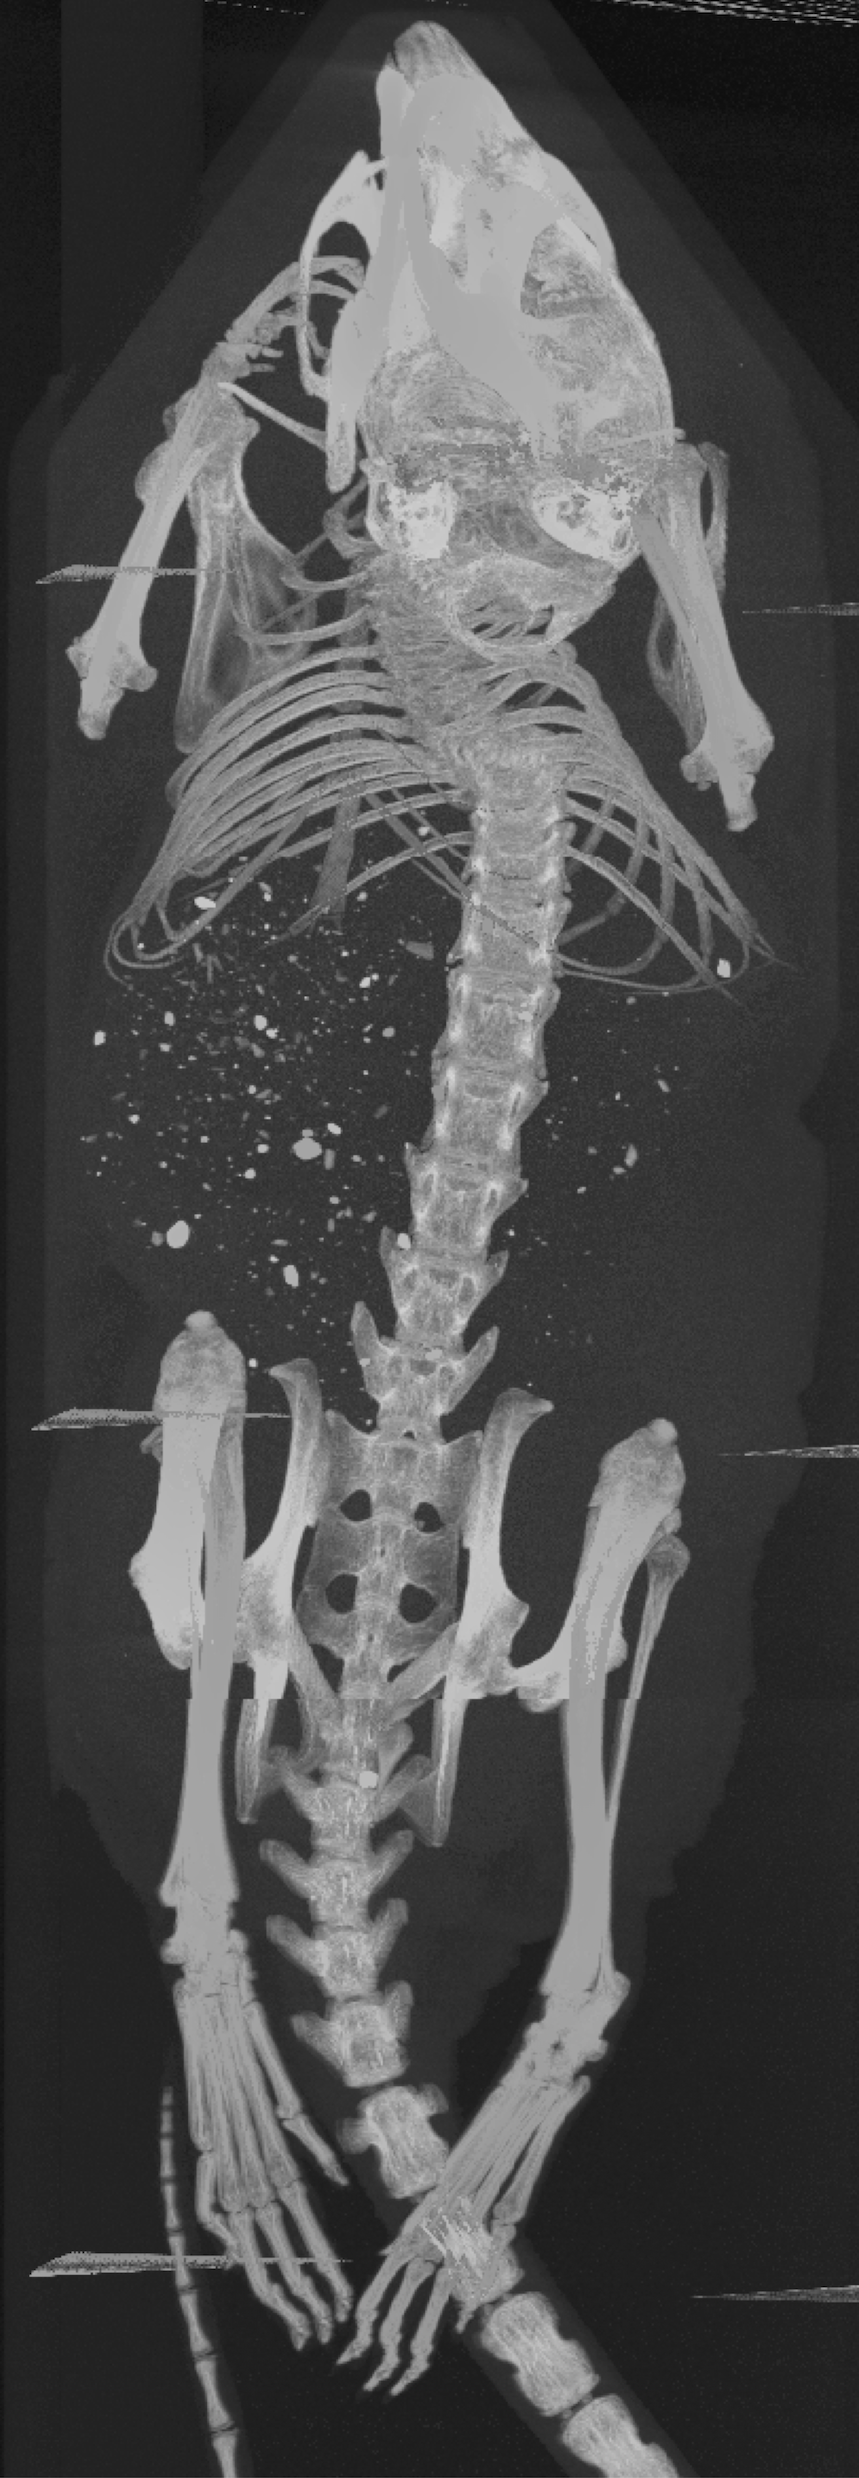

We received two of the mice, hereinafter labeled as A and B, from the UCSF study. Mice A and B were injected with 202020 kBq of 225Ac-Macropa-PEG8(7)-YS5 and 225Ac-DOTA-YS5, respectively. Following injection, mice A and B were euthanized at 222 and 444 days, respectively. The mice were each housed in a 505050 mL falcon tube and stored in a freezer at 7superscript7-7^{\circ}C when not in use.

The two mice were each imaged in the coded aperture and Compton modes to determine the feasibility of using these modalities to assess the daughter redistribution of 225Ac in small animals. The coded aperture and Compton images are overlaid with CT scans. CT imaging was performed separately from the gamma-ray measurements using a MILabs U-CT system; thus, the co-registration is not precise. The following describes the experiments and results in more detail.

Fig. 6a shows the experimental setup of mouse A in the coded aperture mode at 222 days post-injection. The falcon tube containing mouse A was centrally positioned on top of a rotating mount in an upright orientation. The rotation axis was located at a distance of 959595 mm from the mask with the mask positioned at a distance of 505050 mm from the detector. In this configuration, the resolution of the coded aperture imager theoretically should be about 6.96.96.9 mm in FWHM. The mount was rotated in 45superscript4545^{\circ} increments. At each rotation, 4.2×1034.2superscript1034.2\times 10^{3} events were acquired on average at the 218218218-keV emission line of 221Fr after 606060 minutes. The total imaging time amounted to 888 hours.

Fig. 6b shows mouse A in the Compton mode at 444 days post-injection. To maximize the imaging sensitivity and resolution, the falcon tube was positioned as close as possible to the detector in an upright orientation. The central axis of the tube was located at a distance of 353535 mm from the surface of the first detector. In this configuration, the resolution of the Compton imager theoretically should be about 4.14.14.1 mm in FWHM. The falcon tube was rotated by hand in 45superscript4545^{\circ} increments. At each rotation, 4.1×1034.1superscript1034.1\times 10^{3} events were acquired on average at the 440440440-keV emission line of 213Bi after 757575 minutes. The total imaging time amounted to 101010 hours.

Using ML-EM with TV, the two mice were reconstructed in 3-D from the coded aperture and Compton data at the 218218218-keV emission line of 221Fr and 440440440-keV emission line of 213Bi, respectively. Both the coded aperture and Compton images were generated from all eight projections after 250250250 iterations. Figs. 7b-c and 8b-c show the maximum intensity projections (MIP) of the gamma-ray images of mice A and B, respectively. These images are fused with a CT MIP. Furthermore, Figs. 7e-f and 8e-f show coronal slices of the gamma-ray images of mice A and B, respectively. These images are fused with a coronal CT image. The quantification factor, determined from the phantom measurements in Section III-A, was applied to each image so that the intensity scale is in units of percent injected activity per cubic centimeter (%IA/cc). Additionally, the intensity scales are decay corrected to the day of injection.

Figure 7: (a) CT MIP of mouse A fused with the (b) coded aperture (CA) and (c) Compton (CI) MIPs. (d) CT coronal slice of mouse A fused with coronal slices of the (e) CA and (f) CI images. The CA image was generated from a total of 3.4×1043.4superscript1043.4\times 10^{4} events at 218218218 keV, and the CI image was generated from a total of 3.3×1043.3superscript1043.3\times 10^{4} events at 440440440 keV. The intensity scales are decay corrected to the day of injection.